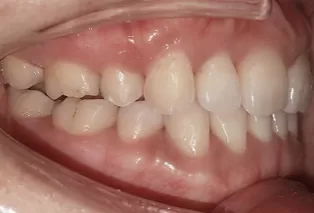

Photos intra-orales